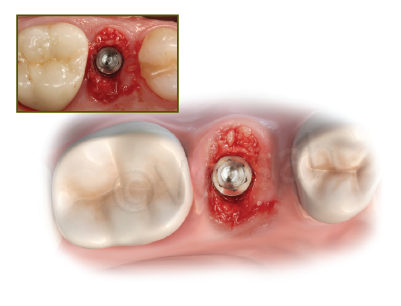

발치 즉시 임플란트

발치와 동시에 임플란트를 식립하며 자가치아로 공간 충전

주요 장점

- 수술 횟수 최소화

- 치료 기간 단축

- 최적의 골유착